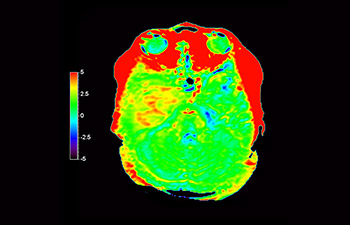

3D APT (Amide Proton Transfer) is a unique, contrast-free, brain MR imaging method addressing the need for more confident diagnosis in neuro oncology. 3D APT uses the presence of endogenous cellular proteins, to produce an MR signal that directly correlates with cell proliferation, a marker of tumoral activity. 3D APT can support trained medical professionals in differentiating low grade from high grade gliomas and, in differentiating tumor progression from treatment effect1.

3D T1w TFE 3D APT